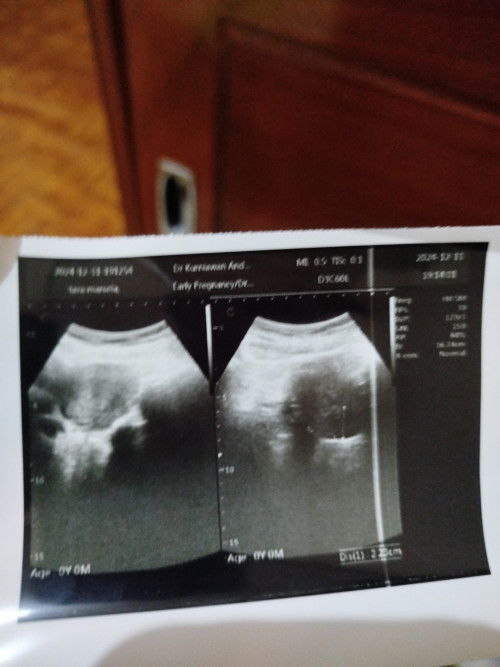

Usg 4minggu belum terlihat kantung janin

Nyoba usg di kehamilan usia 4minggu tapi belum keliatan apa2 bun.. Kata dokternya cuma rahim nya udah membesar.. Disuruh balik lagi usg bulan depan.. Jadi H2C saya tuh.. Dulu pas kakaknya umur usg umur segitu udah keliatan kantung janinnya.. Pokoknya udah mabok parah.. Kalo yg sekarang masih biasa. Ga ada mual, malah nafsu makan makin tinggi.. Ada yg sama ga bund